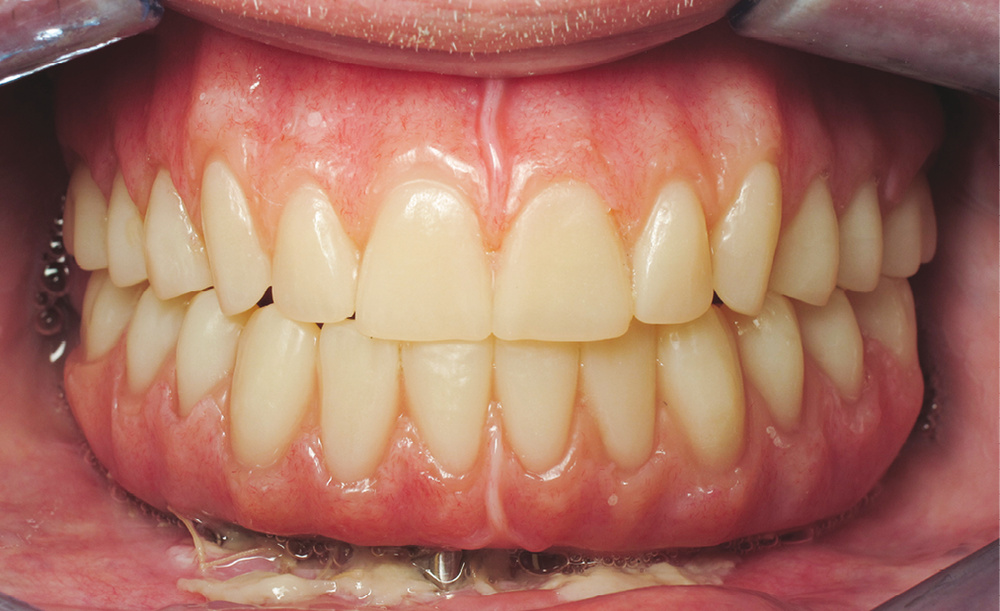

Après démontage et nettoyage du dispositif implantoporté, la barre Trefoil est vissée passivement [7] sur ses analogues grâce à un mécanisme judicieux de rotules compensatrices. Un dernier contrôle de coaptation barre/prothèse est réalisé (fig. 6). L’ensemble est sablé et solidarisé par une résine chémopolymérisable. Après polymérisation, suppression des extensions, aménagement des accès prophylactiques et maquillage composite par addition acté, le bridge d’usage est mis en charge immédiatement (fig. 7).